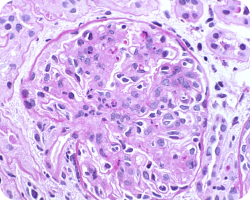

Связь гистологических характеристик по шкале MEST с клиническими аспектами IgA-нефропатии20:

Мезангиальная пролиферация

icon

Течение заболевания у пациентов с мезангиальной пролиферацией (М1) и даже низкой протеинурией ≤ 1 г/день характеризуется схожим прогнозом, как у пациентов со стойкой протеинурией от 1 до 2 грамм в день. Таким образом, несмотря на более низкую экскрецию белка, в первом случае можно говорить о более высоком риске, а также о возможной пользе более ранней иммуносупрессии, потенциально улучшающей сохранение массы нефронов42.